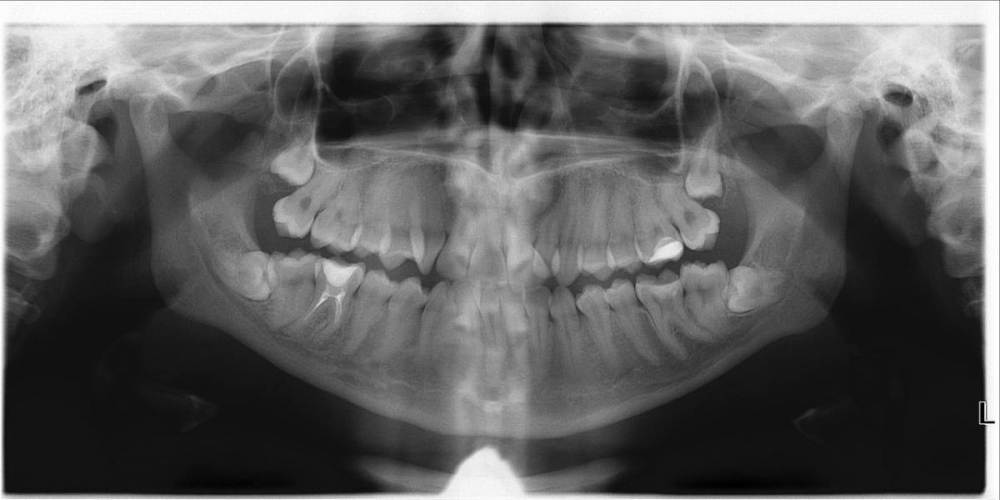

Здравствуйте,появился темный твердый налет около десны. Оказалось, на некоторых зубах с другой стороны тоже такое есть, и по ощущениям будто есть и между некоторыми зубами. Из симптомов только небольшое воспаление десны, но там рядом у меня лезет зуб мудрости под неправильным углом,что и может быть причиной. В какой момент это появилось сказать сложно, полгода назад делала рентген, подобных проблем не было. На холодное\горячее зубы не реагируют, жевать не больно. Подскажите, что это, какой-то вид кариеса? Возможно ли еще неинвазивное лечение или уже поздно?

Здравствуйте, очень похоже на зубной налёт, притом мягкий, который даже Вы сами в дома можете соскрести. Подойдите на осмотр к стоматологу, там точно проверят. В идеале сделать проф.гигиену.

У Вас ещё, кстати, на нижнем дальнем зубе справа (на котором пломба) - есть проблемы на корнях